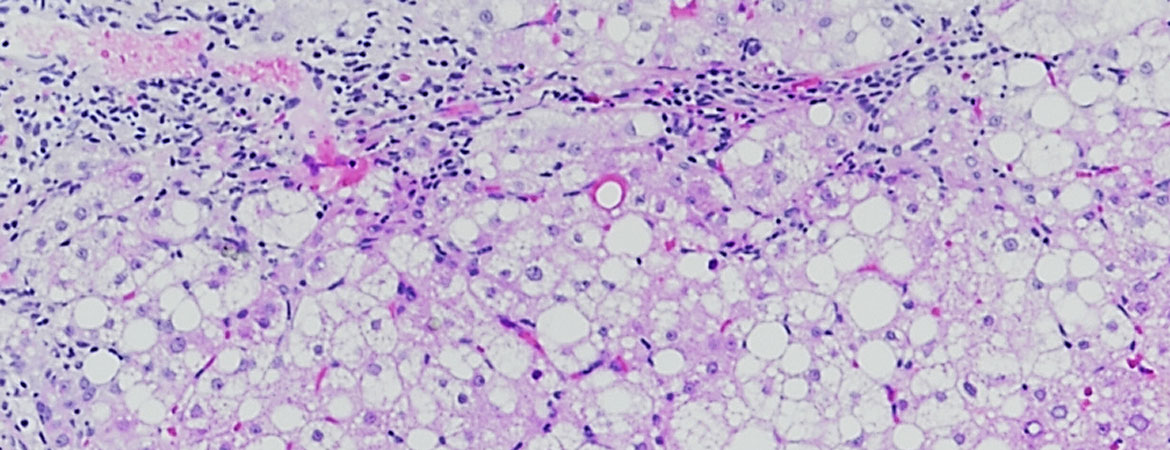

Joana Vieira Barbosa, Montserrat Fraga, Joan Saldarriaga, Philippe Hiroz, Emiliano Giostra, Christine Sempoux, Peter Ferenci, Darius Moradpour (Author) Hepatic manifestations of Wilson’s disease: 12-year experience in a Swiss tertiary referral centre Fulltext PDF Fulltext HTML